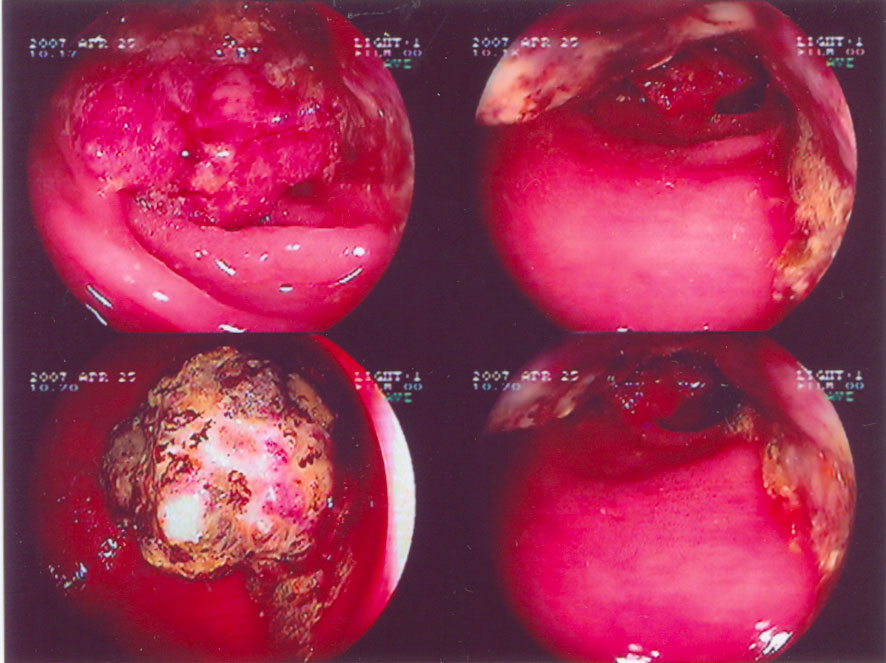

At the end of April 2007, she kept complaining of stomach discomforts, bloatedness and loss of appetite. She saw a Gastro-specialist and the diagnosis was H. pyroli infection and she was given antibiotic treatment. Unexpectedly, an X-ray test was also done and her lung was found abnormal. She did a CT scan and blood test including tumor markers on that same day. The results showed a possibility of lung cancer. One week later she did a lung biopsy. The result showed that the lung tumor mass was a moderately differentiated adenocarcinoma. However, she didn’t have breathing problems or coughs at that time.

She was then referred to an oncologist at the same hospital. My mum is an Asian woman with non-smoking history and the tumor type is adenocarcinoma. Hence she falls into the category that may respond well to a new targeted drug (Tyrosine Kinase inhibitor) called Iressa. The doctor said we can monitor her progress using CA15.3, the tumor marker with highest titer when first found (5147 on 24 April 2007).

After one month of taking Iressa, her CA15.3 went down to 367 (on 28 May 2007). On 30 July 2007, it declined further to 68.  We were so happy that the drug worked so well. A CT scan showed that tumor had shrunk (August 2007). At the forth month, the CA15.3 raised to 154 (on 27 August). The doctor was a bit worried but mum continued taking Iressa. A month later the marker rose to 713 (on28 September 2007). A CT scan showed more shadow in the lung compared to scan done in August 2007. She did a brain CT scan for the first time and some metastases were found in the brain and bones but the lesions were small.